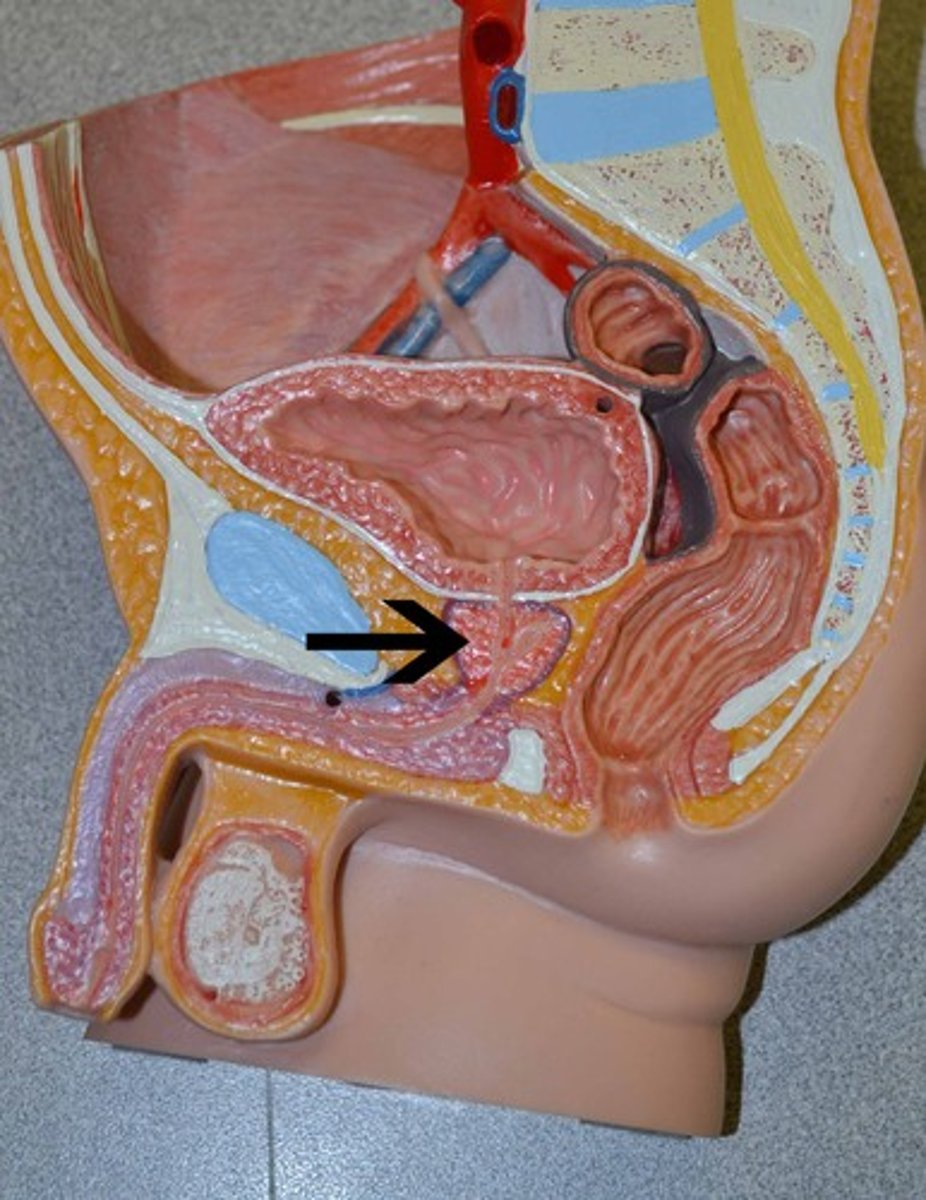

Chapter 30 Anat Phys: Male Reproductive System

Prostate gland

Prostatic urethra